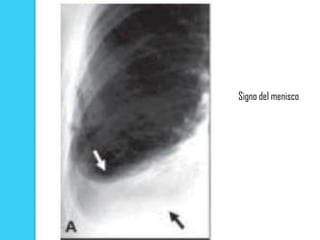

Signo del menisco

   En la radiografía en bipedestación se puede observar un menisco cuando

existe presencia de una pequeña cantidad de líquido en el espacio pleural

La existencia de una línea fina, claramente definida, producida por el margen externo de la pleura visceral, la cual representa el límite del pulmón, separada de la pleura parietal a nivel de la pared costal por un espacio lleno de aire, en la proyección AP  La parte superior de la línea se incurva hacia el ápex pulmonar  Hiperclaridad, secundaria a un espacio interpleural  Habitualmente existe desplazamiento mediastínico, descenso o aplanamiento de la curva diafragmática ipsilateral y ensanchamiento de los espacios intercostales  Ausencia de vasos entre el límite del pulmón y la pared torácica  En la radiografía en bipedestación se puede observar un menisco cuando existe presencia de una pequeña cantidad de líquido en el espacio pleural